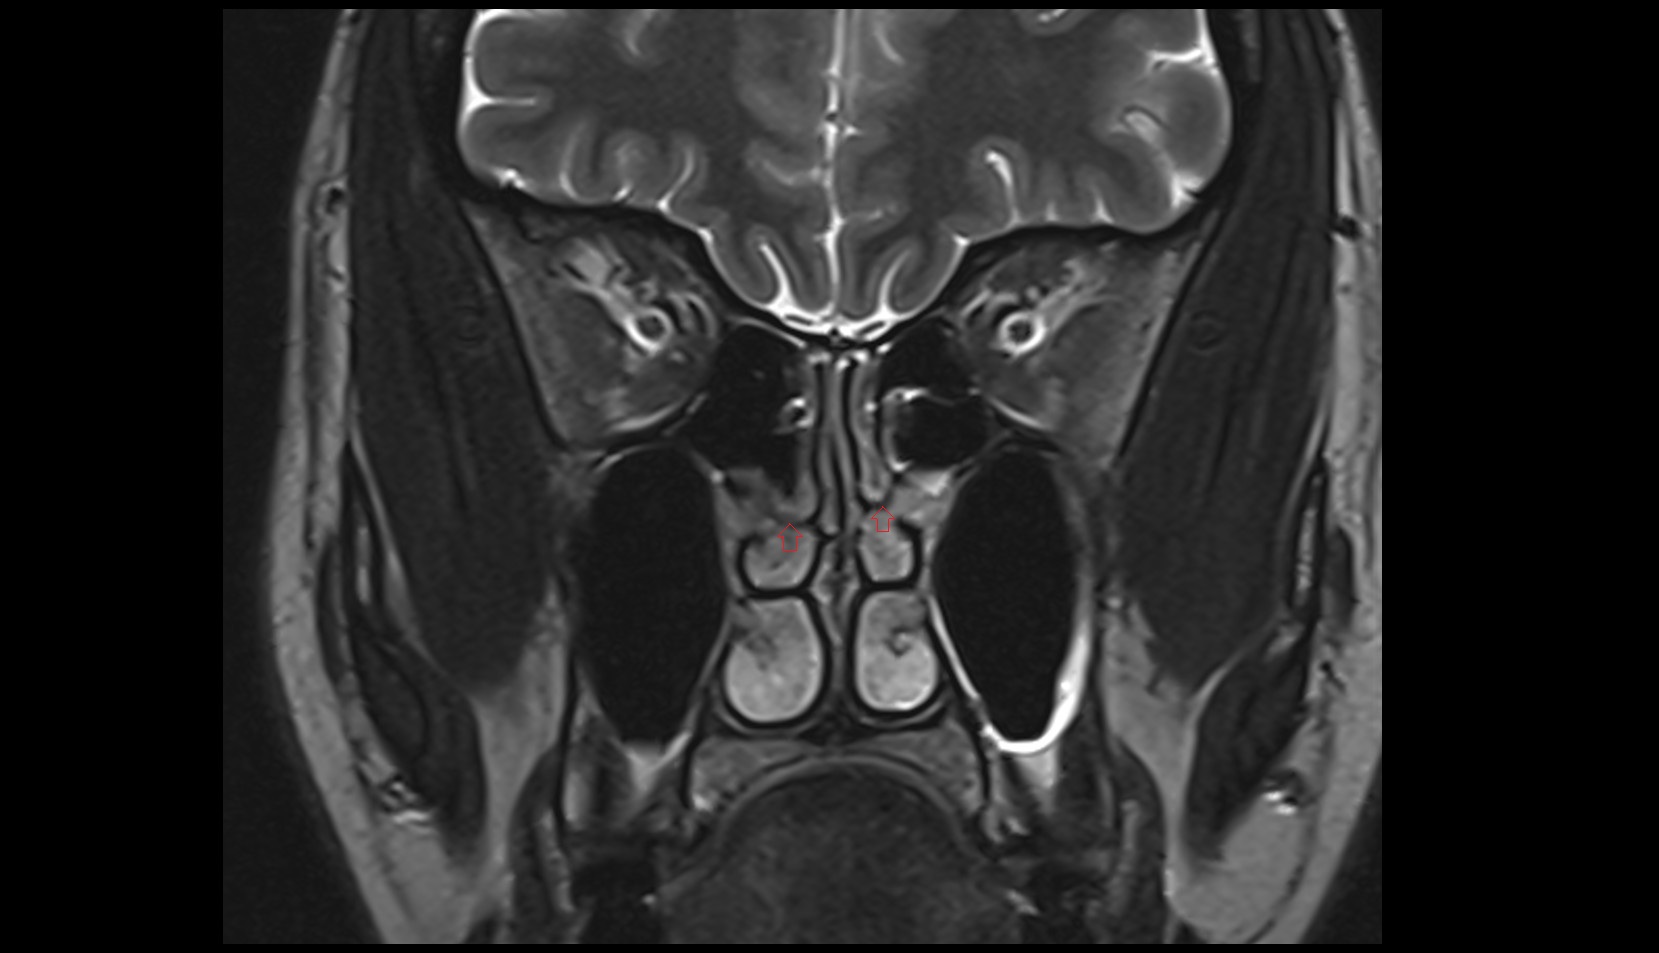

- Hippocampus

- Body of hippocampus

- Head of hippocampus

- Tail of hippocampus

- Hippocampal body

- Hippocampal head

- Hippocampal tail